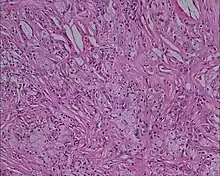

Histologie (Microscopie)

- Infiltrat dermique d'histiocytes géants parfois polynucléés (cellules de Touton) dont le cytoplasme spumeux est chargé de lipides : cholestérol essentiellement